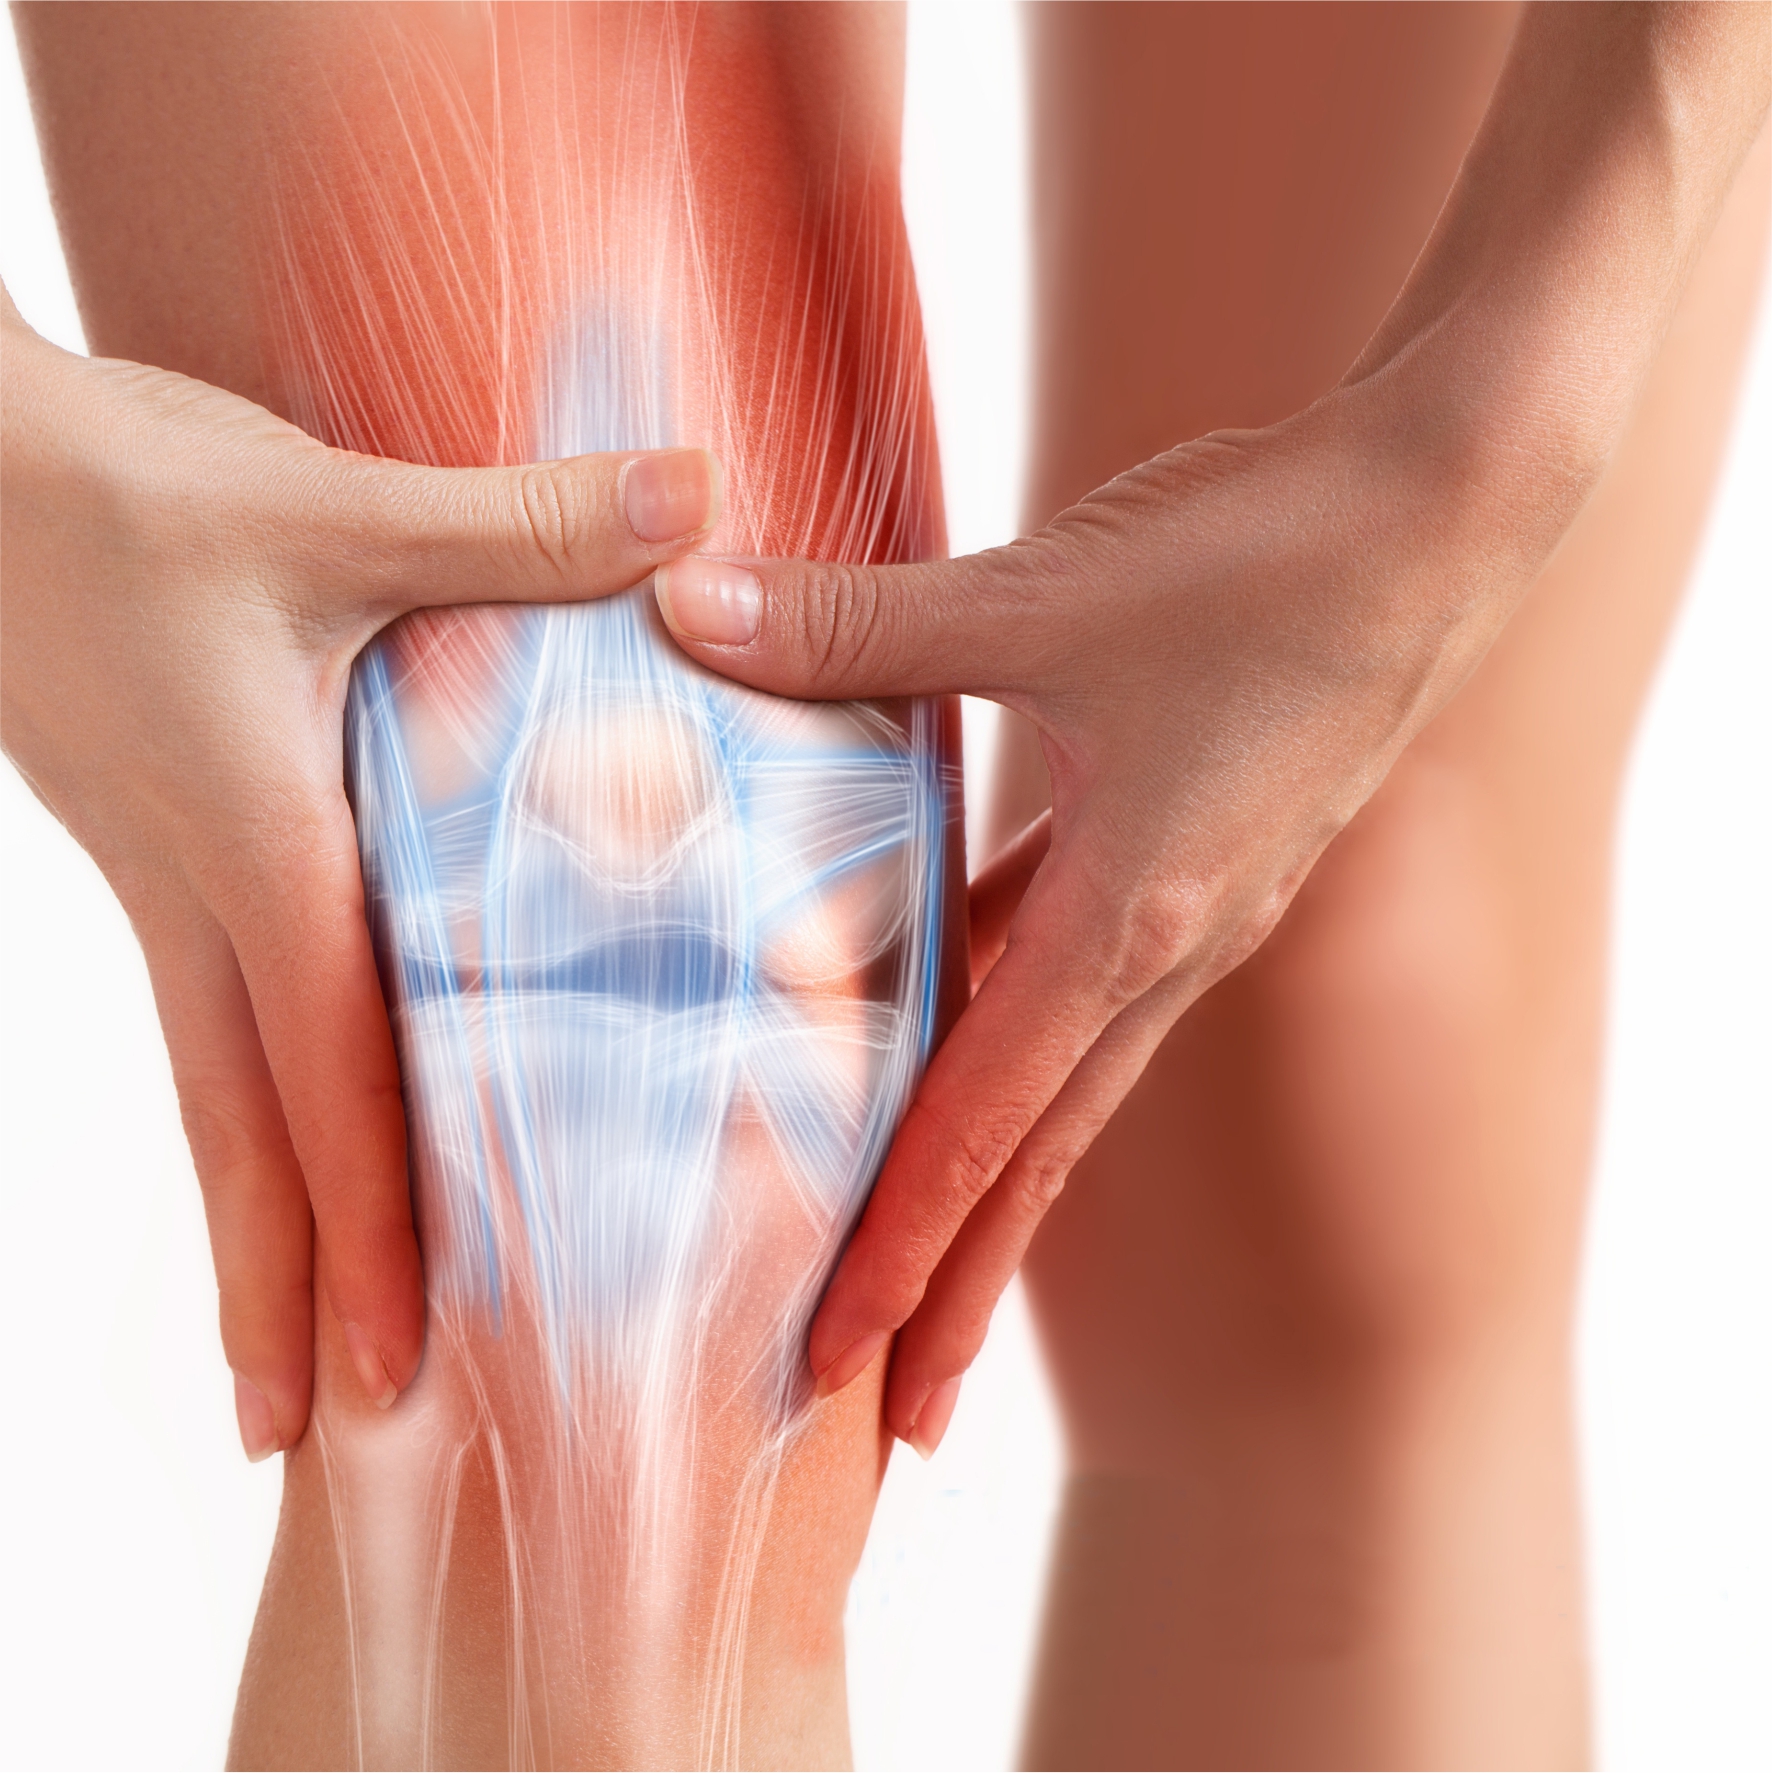

در مطالعه ای که نتایج آن در ژورنال تخصصی جراحی ارتوپدی سال 2015 منتشر شده است ، بین تزریق پی.آر.پی (PRP) و کورتون (CS) در مبتلایان به آرنج تنیس بازان مقاوم به درمان مقایسه ای انجام شد . بیماران با سابقه بیشتر از 6 ماه که به درمان خوراکی رایج هم پاسخ نداده بودند، علاوه بر درجه بندی ضایعه VAS, DASH score ، توسط التراسونولوژیست متبحر اسکلتی-عضلانی از نظر ضخامت تاندون، اثرات خورندگی کورتون ، تحلیل رباط ها و... دسته بندی شده اند.

در مورد پی.آر.پی در این پیگیری 6 ماهه هنوز علائم پدیدار نشده بودند . نتیجه متمایز و بسیار مهم در این مطاله از یافته های سونولوژی بود . که در ان بعد از 6 ماه در گروه PRP یافته های التراسونولوژی در ترمیم تاندون به صورت معنی داری بهتر شده بود ولی در گروه کورتون تعداد بیماران با کاهش ضخامت تاندون افزایش یافته بود و تحلیل نواحی از تاندون هم افزایش پیدا کرده بود.

در نهایت این مطالعه PRP را به عنوان درمانی ارجح تر معرفی میکیند که علاوه بر اینکه عوارض تحلیل روندگی کورتون در دراز مدت را ندارد بلکه با تاثیر در تولید کلاژن ، فراخوانی سلول های مزانشیمی ، تعدیل ایمنی و همچنین اثر فاکتورهای رشد برروی تنوسیت ها ، باعث افزایش بازسازی بافت تاندون هم می شوند.